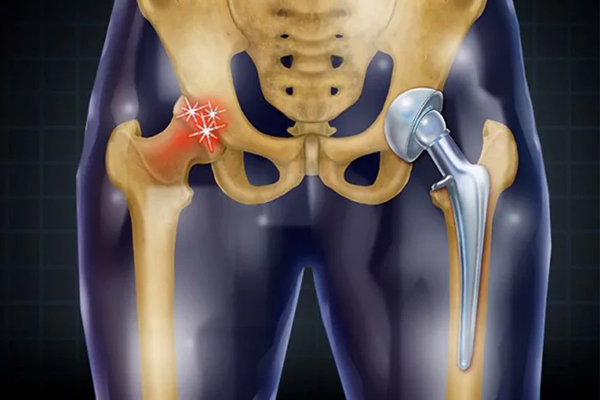

تعویض مفصل لگن یکی از رایجترین جراحیهای ارتوپدی است که به ویژه در سالمندان انجام میشود. این عمل جراحی با هدف بهبود کیفیت زندگی، کاهش درد و بازگرداندن عملکرد طبیعی مفصل لگن در افرادی که از مشکلات حاد مفصلی رنج میبرند، انجام میشود. در این مقاله به مزایا، فرآیند جراحی و مراقبتهای لازم پس از تعویض مفصل لگن در سالمندان میپردازیم.

با افزایش سن، تغییرات طبیعی در استخوانها و مفاصل رخ میدهد که میتواند منجر به مشکلات جدی مانند آرتروز، کاهش تراکم استخوان و آسیبهای مفصلی شود. یکی از مشکلات شایع در میان سالمندان، تخریب و فرسایش مفصل لگن است که میتواند منجر به درد شدید و ناتوانی در حرکت شود.

تعویض مفصل لگن یا آرتروپلاستی لگن یک عمل جراحی است که در آن مفصل آسیبدیده یا فرسوده لگن با یک مفصل مصنوعی (پروتز) جایگزین میشود. این عمل زمانی توصیه میشود که درد و ناتوانی به حدی رسیده باشد که سایر روشهای درمانی مانند داروها و فیزیوتراپی مؤثر نباشند.

2 برداشتن مفصل آسیبدیده: جراح ابتدا مفصل لگن آسیبدیده را از بدن خارج میکند. این شامل برداشتن سر استخوان ران و بخشهایی از استخوان لگن است که دچار فرسایش یا آسیب شدهاند.

3. نصب مفصل مصنوعی: پس از برداشتن بخشهای آسیبدیده، جراح مفصل مصنوعی را که از جنس فلز، پلاستیک یا سرامیک ساخته شده است، در محل قرار میدهد.